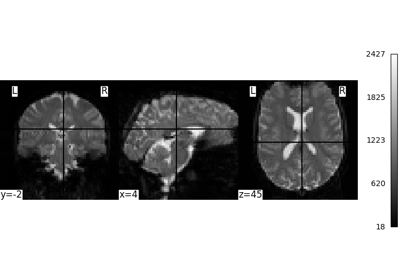

Examples using nilearn.datasets.fetch_spm_auditory¶

Intro to GLM Analysis: a single-run, single-subject fMRI dataset